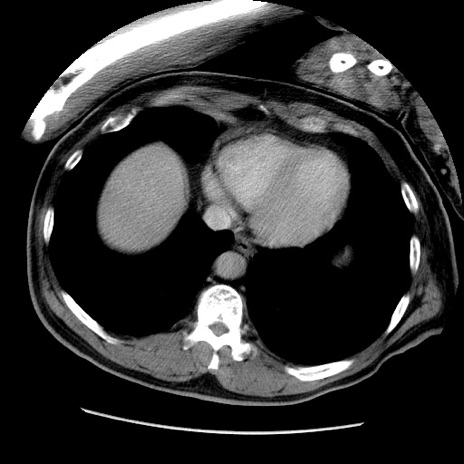

冠状断像